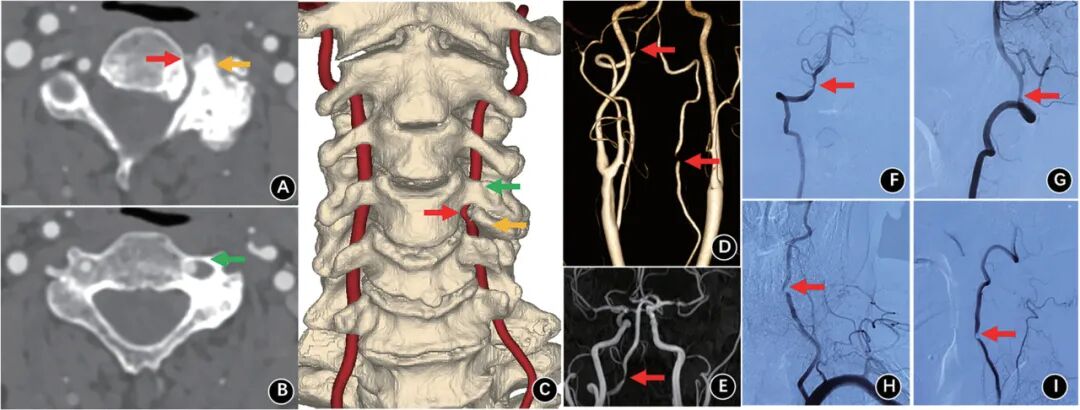

病例报道:77岁男性,出现眩晕、步态不稳和吞咽困难,CTA和DSA显示颈4/5小关节增生压迫椎动脉并95%闭塞。前路椎动脉减压后,椎基底动脉供血不足症状消失。

第二,这例是椎动脉型颈椎病吗?我认为不是。因为,颈椎病的定义是退变性疾病,本文的骨质增生我认为是病理性增生,不应算做退变性增生。增生的原因我估计是小关节慢性低毒性感染,增生的部位是小关节和钩椎关节,横突孔不确切。我对椎动脉型颈椎病的观点在以前的文章中表达过:椎动脉型颈椎病到底存在吗?我国教科书对本病的定义是:因各种机械性与动力性因素(退变性)致使椎动脉遭受刺激或压迫,以致血管狭窄、折曲而造成以椎基底动脉供血不全,引起偏头痛、耳鸣、听力减退及耳聋、眩晕、视力减退、视物模糊、复视等症状。我个人的观点,不认同椎动脉型颈椎病的存在,理由如下:1.教科书描述的横突椎动脉孔骨质增生狭窄压迫椎动脉在理论上不成立。骨质增生本质是关节不稳和异常活动引起慢性损伤,继而骨膜下出血,骨膜细胞、间充质细胞等在细胞因子的作用下向骨细胞分化过程。椎动脉孔没有形成关节,故不会骨质增生和增生性狭窄。2.钩椎关节退变性骨质增生压迫椎动脉,我没有见到文献证据很好的图片。椎动脉毕竟与钩椎关节有一定的距离,而且有较好的弹性,只存在理论上的被压迫。3.旋转椎动脉闭塞综合征(也称为Bow-Hunter’s综合征、Powers’s综合征)是一种少见疾病,因为已有神经内科单独命名,不应归结于椎动脉型颈椎病。4.即使偏头痛、耳鸣、听力减退及耳聋、眩晕、视力减退、视物模糊、复视等症状由椎基底动脉缺血引起,目前文献与颈椎退变有关循证证据并不强,应由神经内科诊断和处理。5.即使有人没有很强证据地猜测交感神经兴奋引起椎动脉痉挛,这怎么说也该由神经内科诊断和处理。第三,时代的进步。1994年新疆医大欧阳甲教授在Spine杂志首次报道椎动脉显露减压治疗15例混合性颈椎病,文后出现大名鼎鼎Magerl的Comment,文中有astonishing这样的字,我猜测这也是随后欧阳甲教授成为大陆首位Spine杂志编委的原因吧(我记忆中,第二位是协和沈建雄教授,第三位是301王岩教授)。本例的图片比当时强太多,而只能发一个case report。